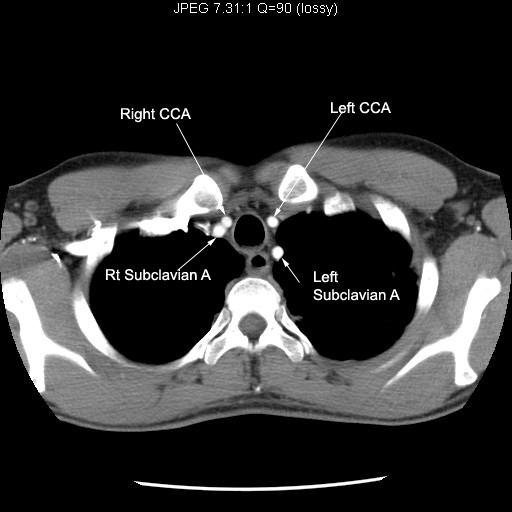

View Chest Ct Scan Anatomy Pics. The ct scanner makes many measurements through the. Scan during the arterial phase.

Set 5 imaging tutorial #2. Filed under anatomy, chest, ct. This includes basic cardiac anatomy and the anatomy of the.